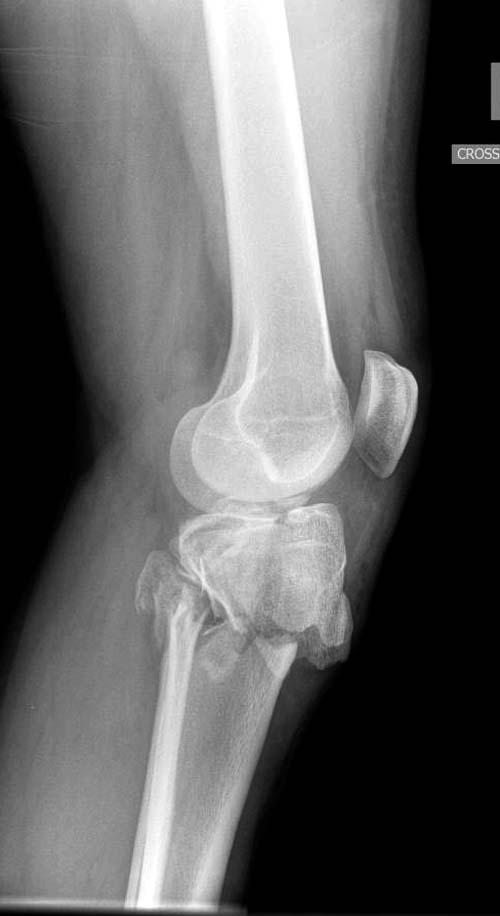

Перелом Schatzker VI является результатом высокой энергии, и здесь кроме мыщелков вовлечен диафиз и мягкие ткани. В данный момент мероприятия по улучшении состояния кожного покрова и мягких тканей можно разобрать вопросы остеосинтеза.

Вытяжение или наружный фиксатор “бедро-голень в виде дельты”. Фиксатор дает свободу, и если условия позволяют, можно отпускать домой. Но главное - надо ожидать проявления “wrinkle sign”! После дистракции можно делать КТ исследование, иначе нестабильные фрагменты искажают данные. Доступ делается по топографии расположения фрагментов, а 3Д картина лучше покажет расположение смещенных мыщелков.

Еще одно дополнение, некоторые в прочтении перелома медиального мыщелка делают типичные ошибки, например, редко переломы медиального мыщелка бывают “только медиальными”, а часто с наличием сложного, заднего компонента, который часто смещается кзади.

На боковом рентгене, явный задний смещенный компонент. КТ поможет увидеть "вершину" перелома, куда надо поставить антискользящую пластину из заднего или задне-медиальнего доступа. Для стабилизации боковой колонны традиционный боковой доступ через Girdle tubercle с длинной блокирующей пластиной. Одна задняя подпорка не удержит медиальную колонну, требуется длинная медиальная пластина.